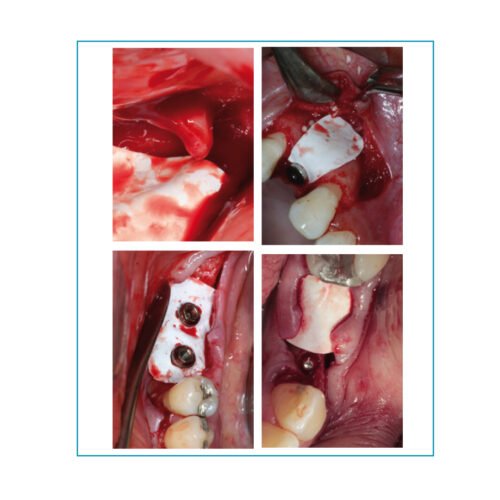

Surgitime PTFE 0,25 mm formato H

Surgitime Titanio 0,15mm

Surgitime Titanio 0,85mm

Surgitime Titanio 0,85mm Bold

Surgitime Titanio Seal